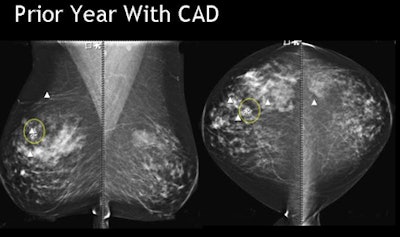

![]() |

| Breast cancer detected by CAD in prior year's mammogram was ignored by the reader. All images courtesy of Dr. Stamatia Destounis. |